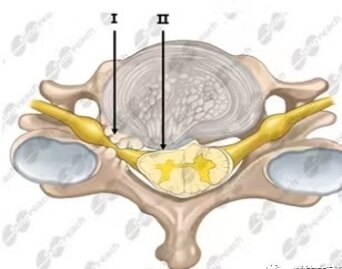

keegan颈椎病又称肌萎缩型颈椎病, 是1965年Keegan JJ教授描述的一种特殊类型的颈椎病。以上肢三角肌、肩胛带肌、肱二头肌或手内在肌、骨间肌萎缩并引起肌力下降为主要临床表现。Keegan颈椎病的病理机制是脊髓前角细胞缺血性损伤和前根(腹侧根)损伤,是感觉运动分离的主要致病原因。下图I为压迫腹侧前根,II为压迫脊髓前角。